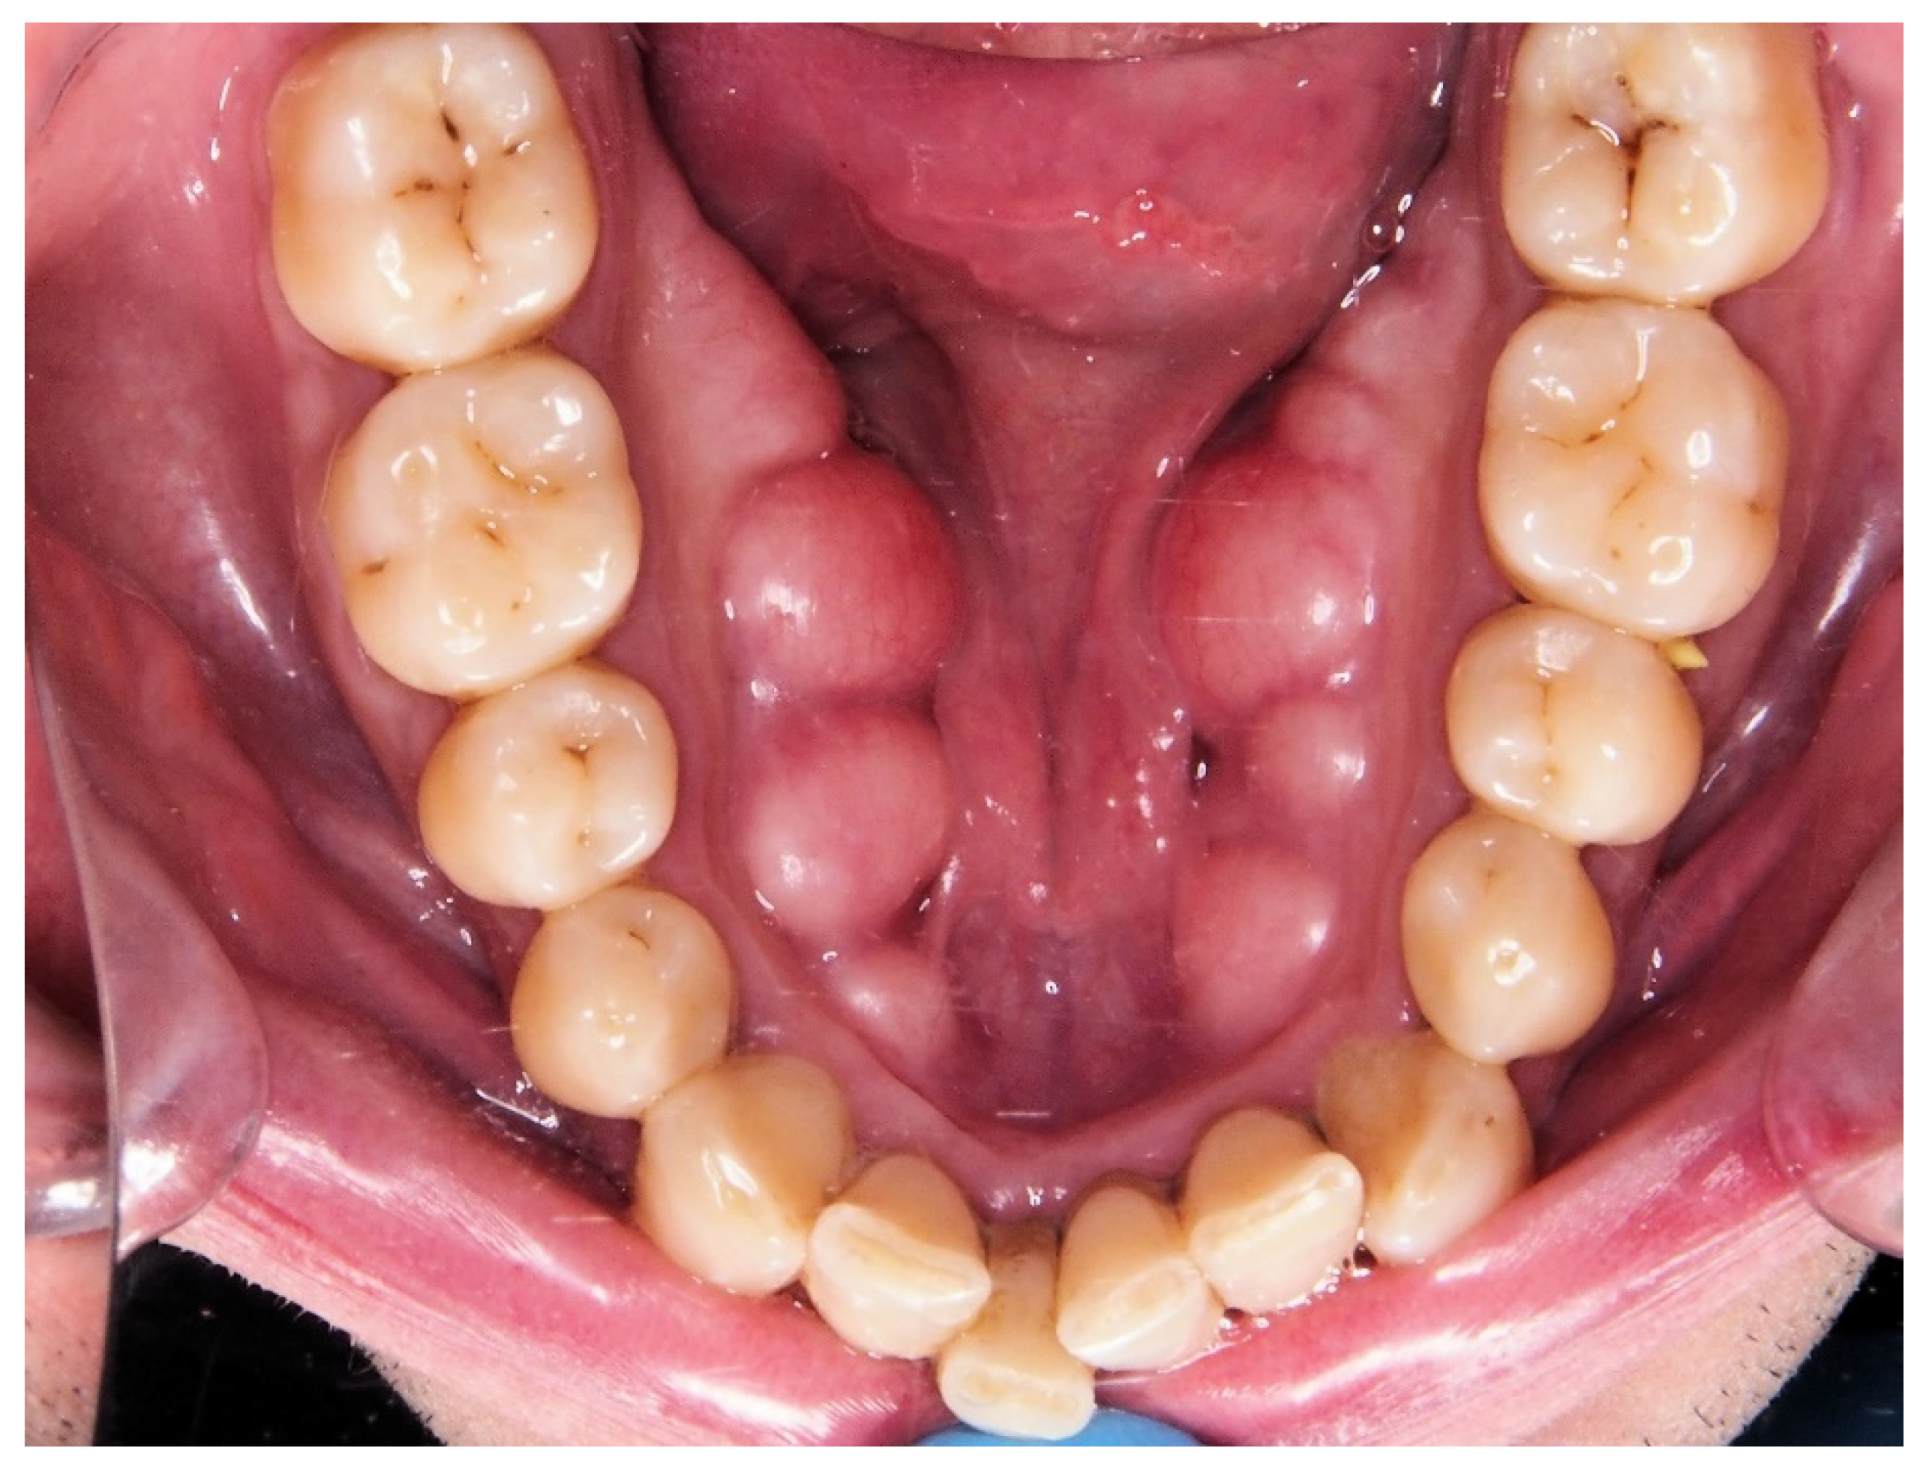

- Choi, Y.; Park, H.; Lee, J.-S.; Park, J.-C.; Kim, C.-S.; Choi, S.-H.; Cho, K.-S.; Chai, J.-K.; Jung, U.-W. Prevalence and anatomic topography of mandibular torus: Computed tomographic analysis. J. Oral Maxillofac. Surg. 2012, 70, 1286–1291. [Google Scholar] [CrossRef]